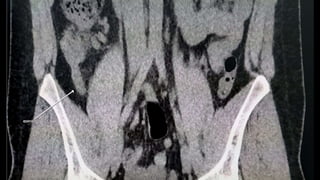

This document discusses the evaluation of right lower abdominal pain and lists appendicitis as a key cause. It notes that other potential causes include hemorrhagic cysts, heterotrophic pregnancy, salpingitis with pyosalpinx, funiculitis, and torsion of an undescended testis. The document was presented by Dr. A.S.M. Sufian of Cumilla Medical College Hospital and thanks the audience for their patience and listening.